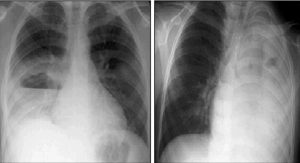

[Sonographic findings of loculations and septations with in effusion shas been shown to correlate with empyema as confirmed by surgical findings and fluid analysis

A chest ultrasound of a 7 yr female which demonstrates a right sided mul-septated, moderate to large, hyperechoic pleural effusion with a thickened visceral pleural ’rind’ appearance.

Computed tomography imaging of a 4yomale with pneumococcal pneumonia (serotype 3) complicated by left sided empyema and bronchopleural fistula.

The imaging demonstrates a left sided hydropneumothorax with consolidaon of the left upper and lower lung segments, and loss of the normal pulmonary parenchyma consistent with a necrosing pneumonia, with a flexible chest drain insitu